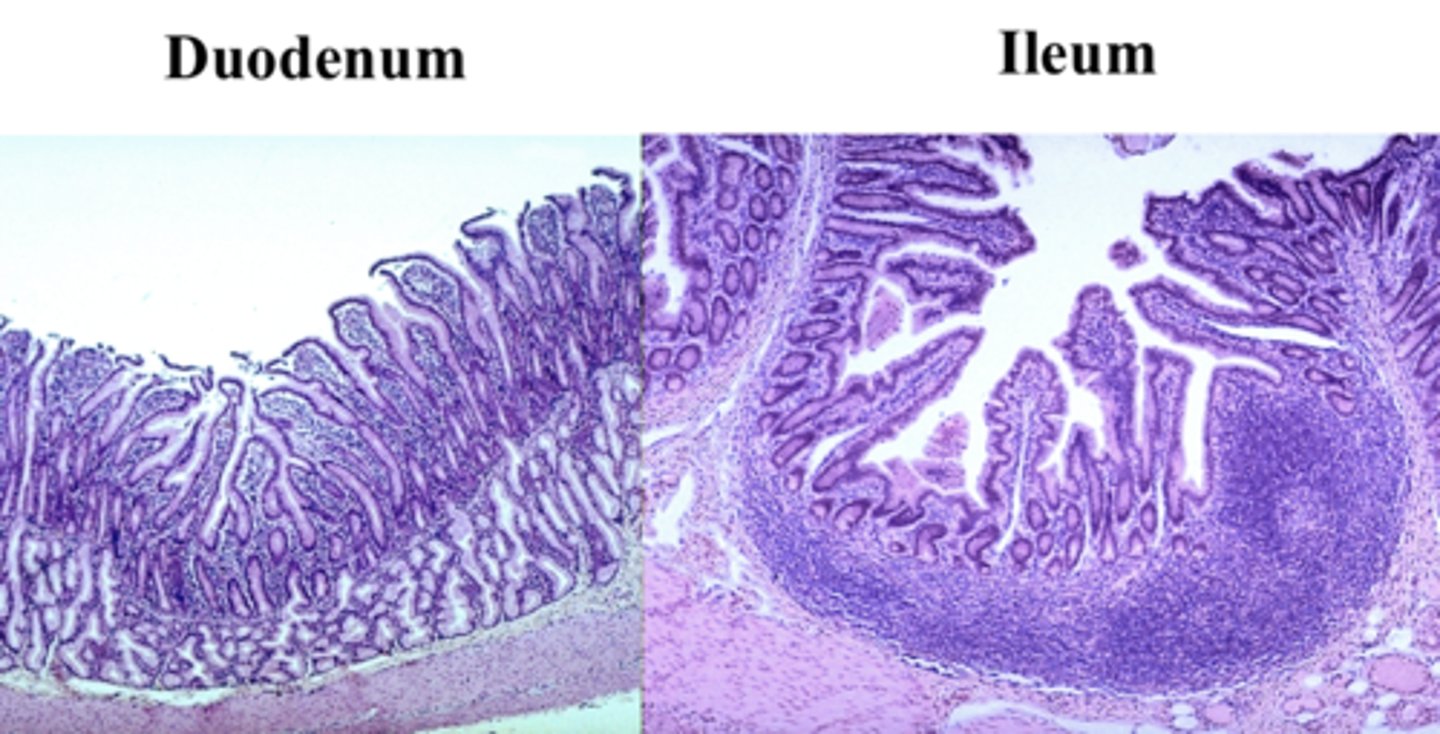

ileum

What is this?

ileum Peyer's patch

What is this?

duodenum

What is this?

jejunum

What is this?

Jejunum has no Brunner's gland or malt tissue

duodenum and ileum vs jejunum